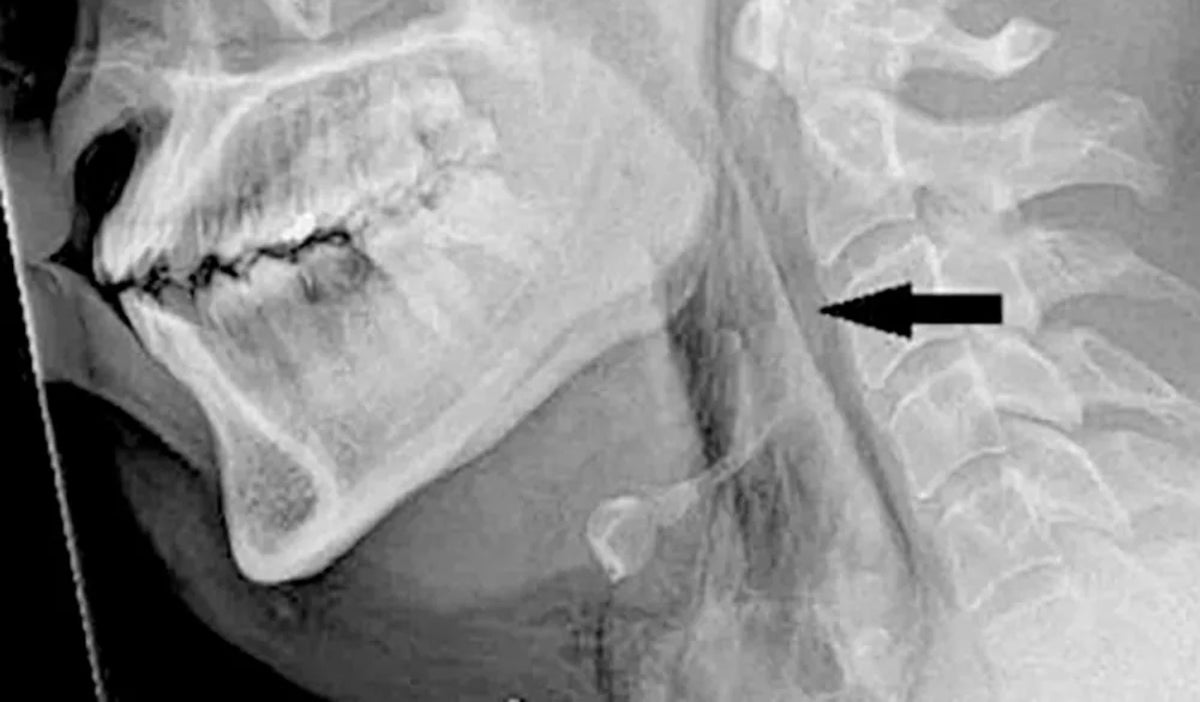

Según la revista mencionada, al parecer, el hombre iba conduciendo cuando sintió muchas ganas de estornudar, pero decidió cerrar la nariz y la boca impidiendo que este saliera, lo que resultó en la acumulación de presión de 20 veces mayor a la que normalmente se genera abriendo un hueco en su tráquea de 2 por 2 milímetros.

Luego de esto, sufrió un dolor e hinchazón, por lo que le realizaron radiografías que confirmaron un enfisema quirúrgico, es decir, que el aire quedó atrapado bajo capas profundas de tejido en el cuello, lo que generó un desgarro traqueal entre el tercer y cuarto hueso de la vértebra torácica.